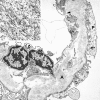

Benefit of anti-TNFalpha treatment for nephrotic syndrome in a patient with juvenile inflammatory bowel disease associated spondyloarthropathy complicated with amyloidosis and glomerulonephritis